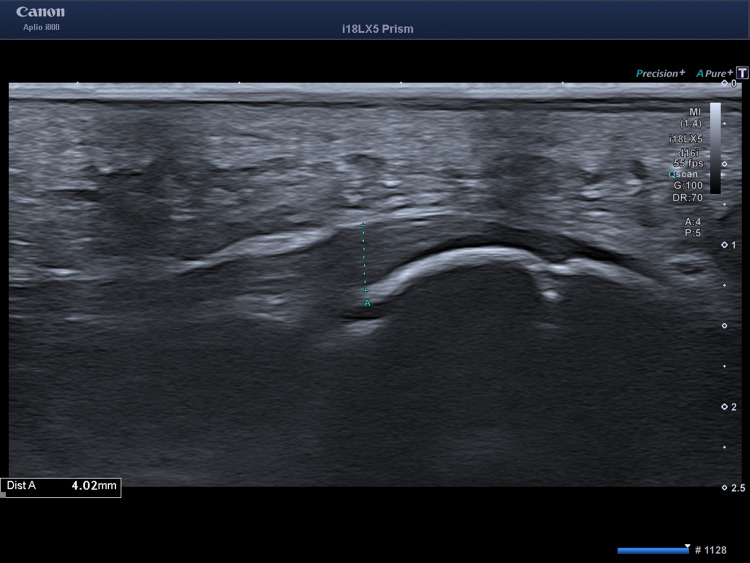

本病例报告描述了一种新颖独特的电磁和电液聚焦体外冲击波疗法(ESWT)与体外磁传导疗法(EMTT)相结合的治疗方法,用于加速一名青少年跑酷运动员胫骨骨骺骨折的愈合。在一次 2.5 米的跳跃后,这名 14 岁的少年出现了明显的足跟疼痛,但他没有告诉父母。八周后,使用超低剂量负重锥形束 CT(WBCT)进行的初步成像显示,在开放的小方骨骨骺附近存在小方骨骨骺不愈合的情况。为了显著改善并加快骨愈合,我们选择了联合使用聚焦电磁(Storz Ultra,Storz Medical AG,瑞士泰格威伦)和聚焦电液(MTS,德国康斯坦茨)ESWT,每周连续五次,同时让患者完全负重。六周后进行的 WBCT 随访显示,延迟结合部接近完全愈合,且无疼痛。值得注意的是,聚焦 ESWT 和 EMTT 联合疗法并没有导致小骨骨骺提前闭合。我们的结论是,聚焦电磁和电液 ESWT 与 EMTT 联合疗法可促进青少年小头骨骺骨折的骨性愈合,而不会对开放的骨骺产生任何不良影响。证据等级 IV(病例报告)。

This case report describes a novel and unique combination of both electromagnetic and electrohydraulic focused extracorporeal shockwave therapy (ESWT) and extracorporeal magnetotransduction therapy (EMTT) for accelerated healing in a calcaneus epiphyseal fracture with delayed healing in an adolescent Parkour athlete. After a 2.5m jump, the 14-year-old experienced significant heel pain, however avoided telling his parents. After eight weeks, the initial imaging using ultra low dose weight-bearing cone beam CT (WBCT) revealed a calcaneus non-union situation adjacent to the open calcaneal physis. To improve and accelerate bony healing substantially, we chose to apply both combined focused electromagnetic (Storz Ultra, Storz Medical AG, Tägerwillen, CH) and focused electrohydraulic (MTS, Konstanz, Germany) ESWT in a fractioned fashion plus EMTT (Storz Magnetolith, Tägerwillen, CH) in five consecutive weekly sessions while allowing the patient to fully weight bear. The follow-up WBCT after six weeks revealed a near to total healing of the delayed union and being pain-free. Notably, combination therapy with focused ESWT and EMTT did not result in early closure of the calcaneal epiphysis. We conclude that combined focused electromagnetic and electrohydraulic ESWT and EMTT facilitate bony healing in adolescent calcaneal apophyseal fractures without any adverse effects on the open physis. Evidence level IV (case report).